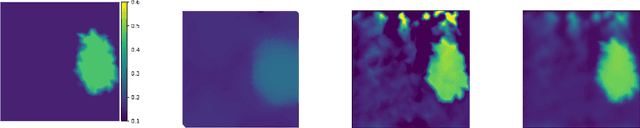

Ultrasound elasticity images which enable the visualization of quantitative maps of tissue stiffness can be reconstructed by solving an inverse problem. Classical model-based approaches for ultrasound elastography use deterministic finite element methods (FEMs) to incorporate the governing physical laws resulting in poor performance in noisy conditions. Moreover, these approaches utilize fixed regularizers for various tissue patterns while appropriate data-adaptive priors might be required for capturing the complex spatial elasticity distribution. In this regard, we propose a joint model-based and learning-based framework for estimating the elasticity distribution by solving a regularized optimization problem. We present an integrated objective function composed of a statistical physics-based forward model and a data-driven regularizer to leverage deep neural networks for learning the underlying elasticity prior. This constrained optimization problem is solved using the gradient descent (GD) method and the gradient of regularizer is simply replaced by the residual of the trained denoiser network for having an explicit objective function with reduced computation time.